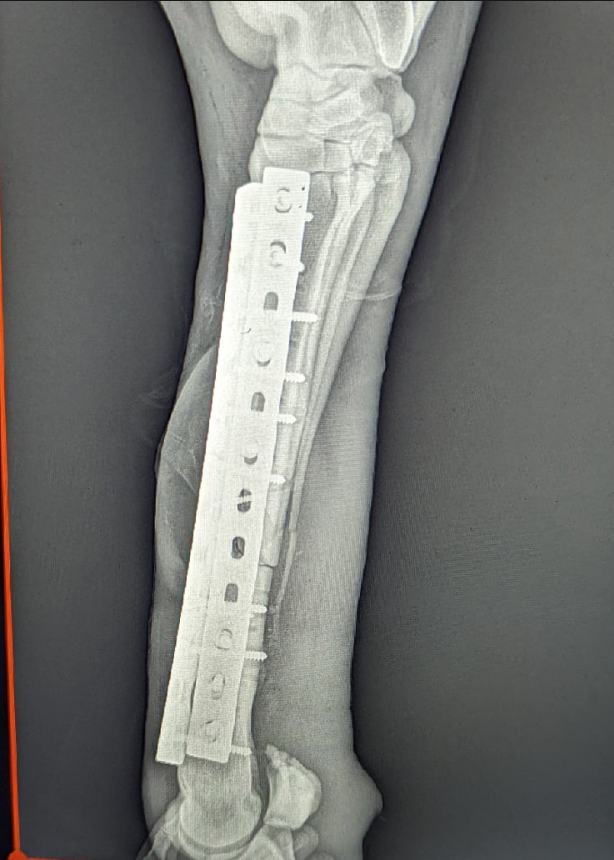

Задача операции состояла в соединении кости двумя бедренными "человеческими" пластинами.

Спустя два часа операция была закончена, нога плотно завернута в вату и бинты, а уже через четыре часа после операции конь смог с помощью четырех человек подняться на ноги, начал самостоятельно есть и пить.

Но на следующий день нас ждал неприятный сюрприз - пластины под весом животного погнулись. Мы просто не ожидали, что такое возможно – ведь брали достаточно большие «человеческие» бедренные пластины.

Учитывая все ошибки прошлого, в тот же день была проведена вторая операция. На этот раз были выбраны самые большие хирургические пластины из всех, которые только возможно заказать у производителя.

Несмотря на сложности повторного хирургического вмешательства, операция прошла успешно - пластины заняли своё место, а нога была дополнительно укреплена не только ватой и тугой повязкой, но и пластиковым гипсом.

2. Пластины необходимо брать самые большие из тех, что сможете найти. Не доверяйте ощущениям - как показала практика, выглядящие действительно надёжно и крепко пластины конь гнёт без особых усилий.